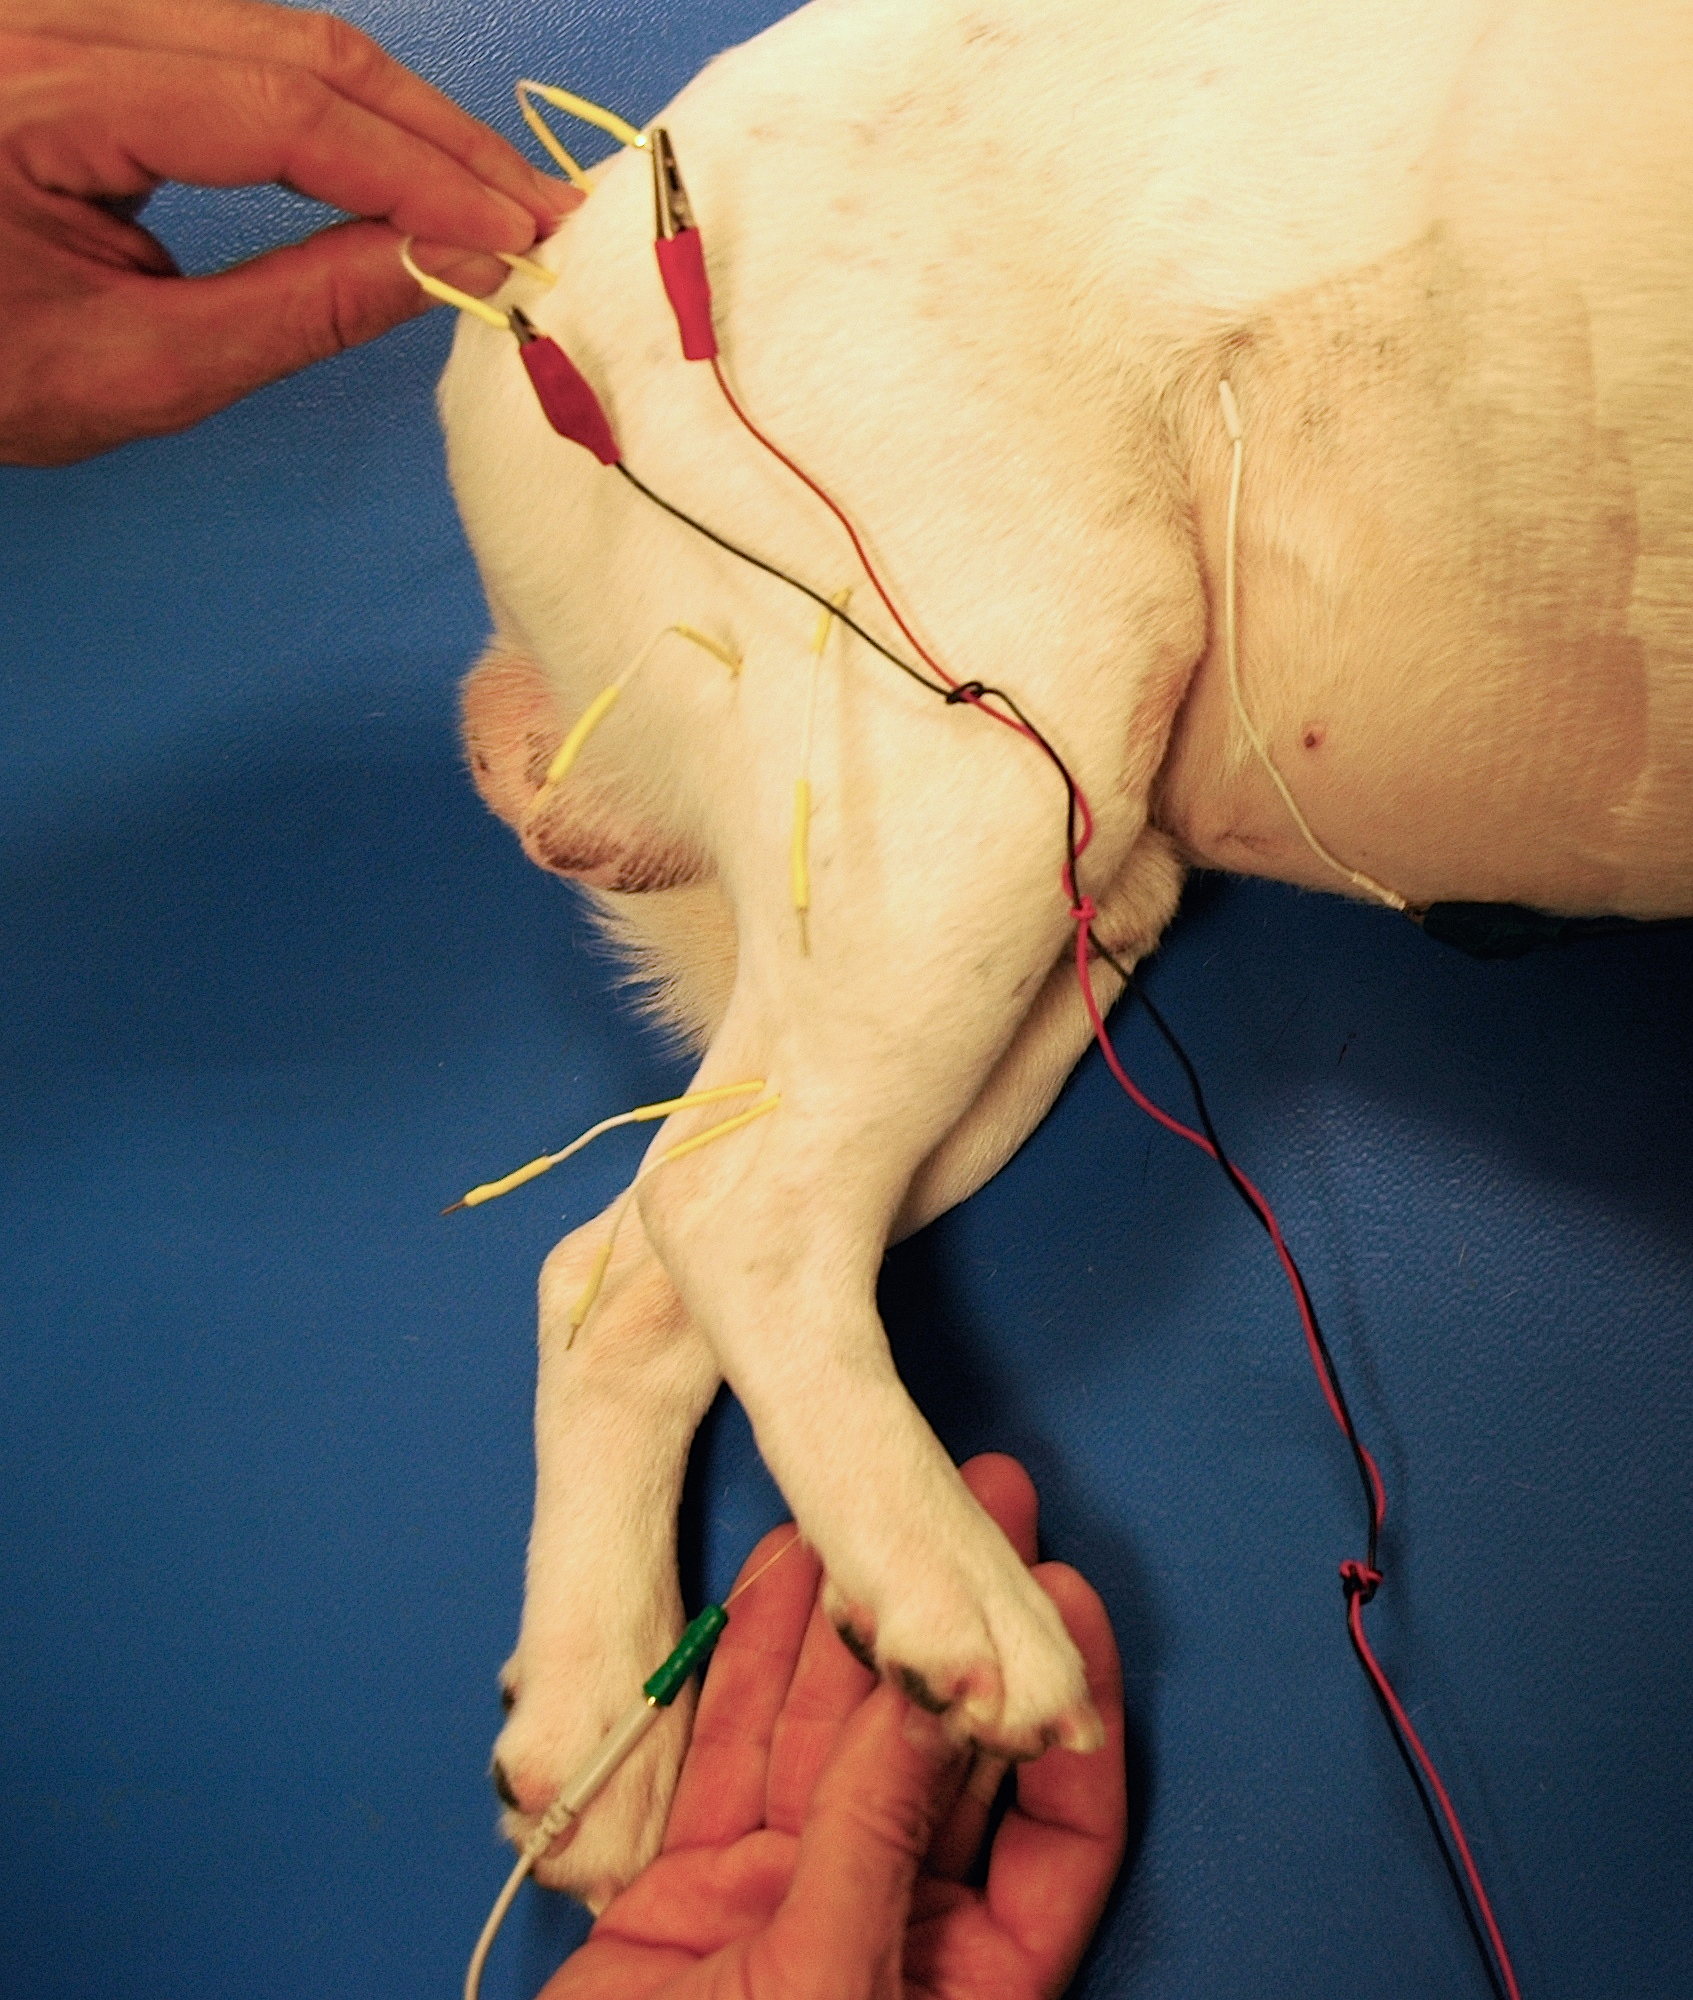

Les études électrodiagnostiques

Les études électrodiagnostiques

Électrodiagnostic

Méthode d’évaluation des structures nerveuses périphériques et neuro-musculaires en utilisant de faibles courants électriques afin de déterminer la présence d’un dysfonctionnement de ces structures.